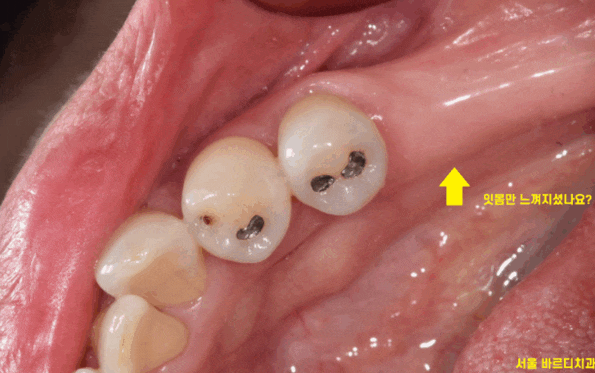

임플란트 수술 후 혀로 수술 부위를 만져보면

잇몸 밖으로 무언가가 튀어나온 것을

확인하실 수 있습니다.

이것은 임플란트는 아니고요~~

임플란트와 연결해둔 뚜껑입니다.

이렇게 뚜껑을 잇몸 밖에 두는 것을

임플란트 1회 수술법이라 합니다.

그도 그럴 것이 사진과 같은 모습이기 때문이죠~!

잇몸밖에 안보이죠~?